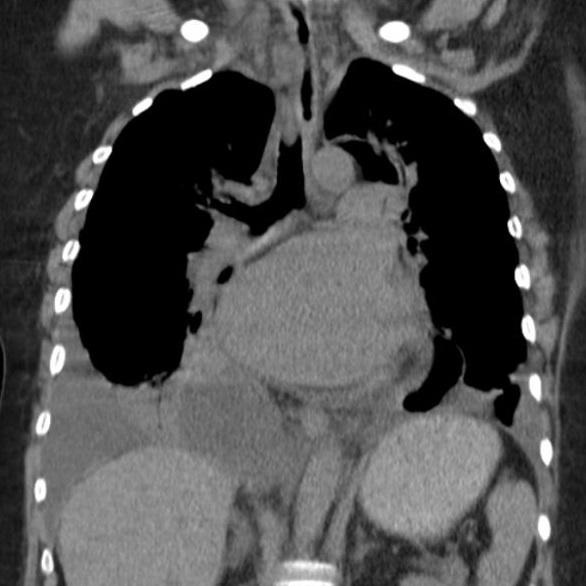

Image radiologique TDM d'une pleuresie du

poumon droit de moyen abondance . La liquide

transudat ou exsudative declive au sinus costo

diaphragmatique lateral et posterieur du poumon

droit en formant de aspect de masse non systematisee

, isopdensite , homogene . Image radiologique

TDM en coupe axiale et coronal , fenetre

mediastinale et image radiologique TDM coronal ,

fenetre parenchymateuse |